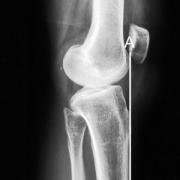

Then a line is drawn perpendicular to the anterior tibial cortex line (B). Finally a line is drawn along the top of the tibial plateau (C), and the angle of the posterior tibial slope is the angle formed by B and C.